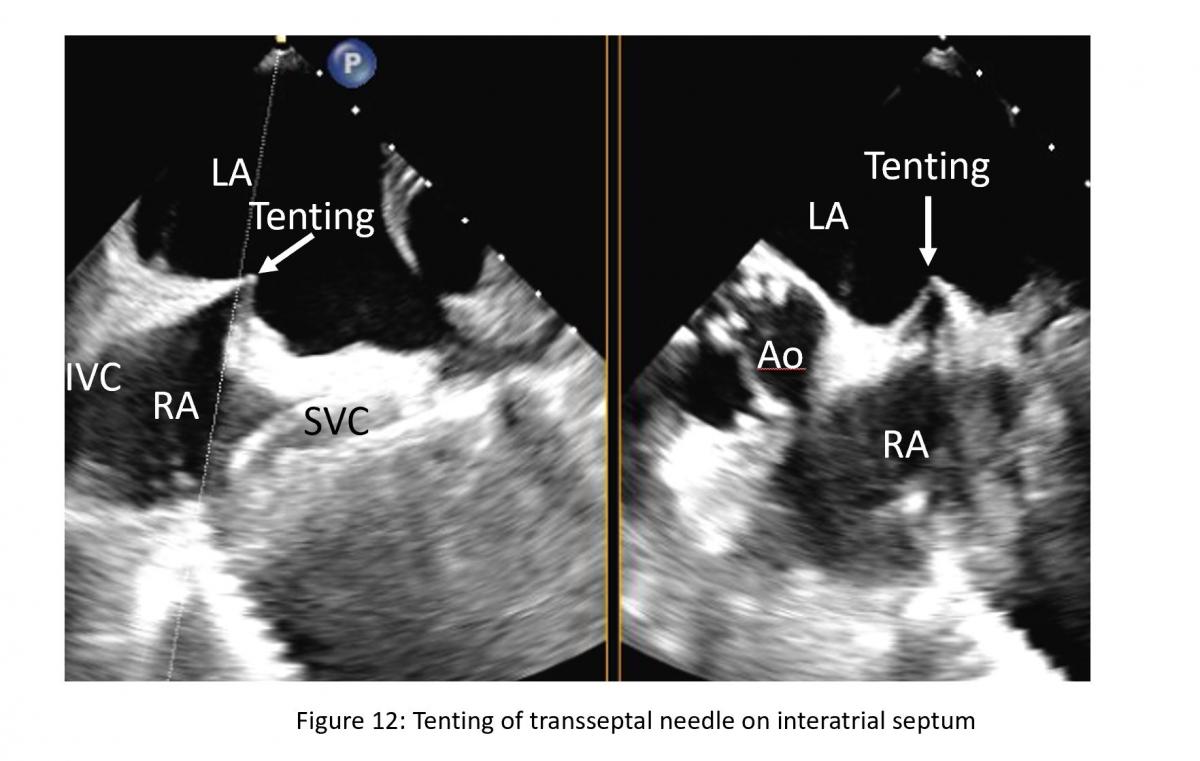

Location of the transseptal puncture is important. The optimal puncture site is in the membranous part of interatrial septum (IAS) superiorly towards the mid septum and posteriorly of the interatrial septum.  The newer clips NTR and XTR requires more mid superior-inferior and posterior septal puncture. Three TEE planes are used to determine the correct site:

• a short-axis view at the base for anterior-posterior orientation; aortic valve in short axis as an anterior landmark

• a bi-caval view for superior (cranial)- caudal (inferior) orientation/110-degree view

• a four-chamber view to direct the height above the mitral valve

Figure 12: Xplane or biplane TEE view of bicaval and short-axis view of aortic valve for atrial puncture guidance. Tenting is hallmark of septal puncture need tip pressing on interatrial septum (IAS). LA: left atrium, RA: right atrium, SVC: superior vena cava, IVC: inferior vena cava.

The position of the BRK transseptal needle (St. Jude Medical, Inc, St Paul, Minnesota, USA) can be seen by a tent-like indentation of the interatrial septum (‘tenting’) (Figure 11) Thereby, the tip of the ‘tent’ points towards the left atrium. With a satisfactory posterior and superior location, the height above the valve is assessed in a four-chamber view (Figure 12).

Figure 13: 4-chamber TEE view from transeptal height (TS)

The site of optimal transseptal puncture is slightly different for PMR and FMR. In structural mitral leaflet disease (e. g. prolapse or flail), the puncture site needs to be 4–5 cm above the mitral annulus to guarantee enough space for adequate catheter and MitraClip maneuvering. In contrast, in cases of functional MR, the line of coaptation is usually below the plane of the mitral annulus due to extensive tethering. Therefore, the puncture site in these patients needs to be more inferior and closer to the annular plane (about 3.5-4.5 cm above the annular plane). Also, a different location of a lesion that cause MR may also require adjustment of septal puncture site (Figure 13).